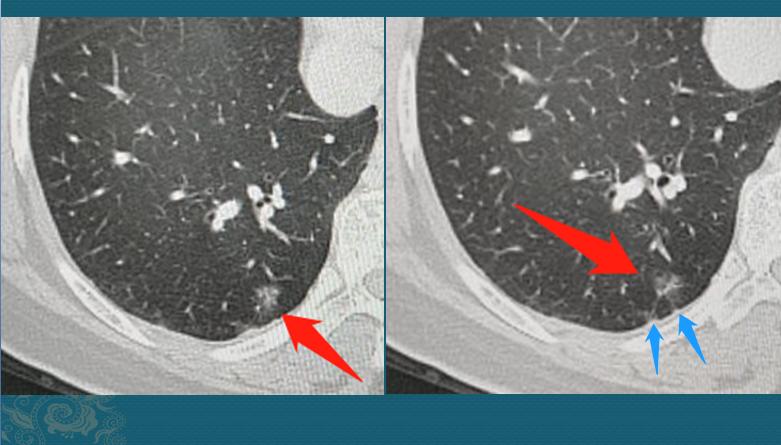

因为疫情缘故,她在8个月的时候回来复查了CT,左边的没有变化,右边的长大了:

8个月的时间,从一个不足3mm的微结节,长成9mm的磨玻璃结节,速度非常快!以至于我们不敢确定就是肺癌。

我们把图像放大再看看细节,这个磨玻璃结节边界不清晰,内部有血管穿行,并略增粗,边缘有两处细线状胸膜牵拉,病人也没有咳嗽、发热症状,炎性指标都正常,这些辅助资料不太支持炎症:

最终做了胸腔镜下切除,病理是微浸润肺腺癌,基本治愈!因为<1cm的微浸润肺腺癌,手术治愈率几乎是100%的。